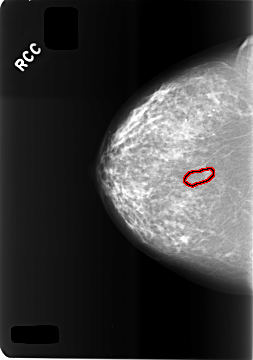

C_0473_1.RIGHT_CC

FILE: C_0473_1.RIGHT_CC.OVERLAY

TOTAL_ABNORMALITIES 1

ABNORMALITY 1

LESION_TYPE CALCIFICATION TYPE FINE_LINEAR_BRANCHING DISTRIBUTION LINEAR

ASSESSMENT 4

SUBTLETY 2

PATHOLOGY BENIGN

TOTAL_OUTLINES 1

BOUNDARY